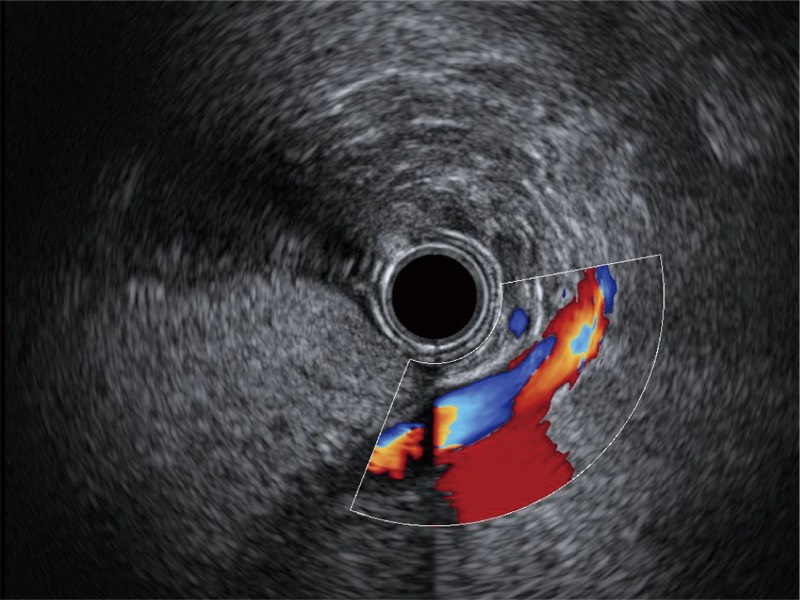

食管内间质瘤清晰显像

清晰显示胆总管及周围血管分布

肝左叶和肝静脉的横截面